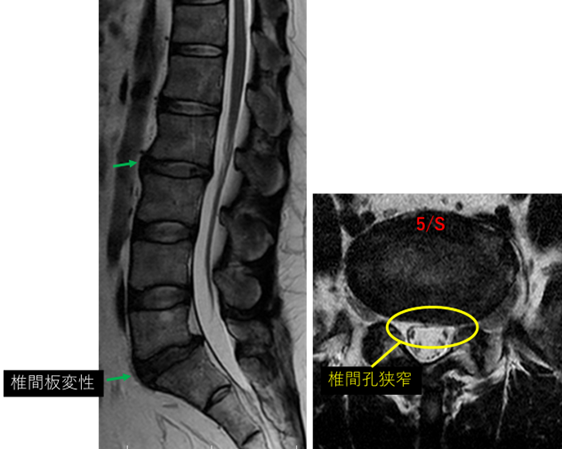

画像及び所見について

L5/S: 変性、膨隆、左椎間孔狭窄

以上の事が画像上認められます。

L2/3、5/S に

変性、膨隆、左椎間孔狭窄 を認め、主症状の原因の可能性が高い。